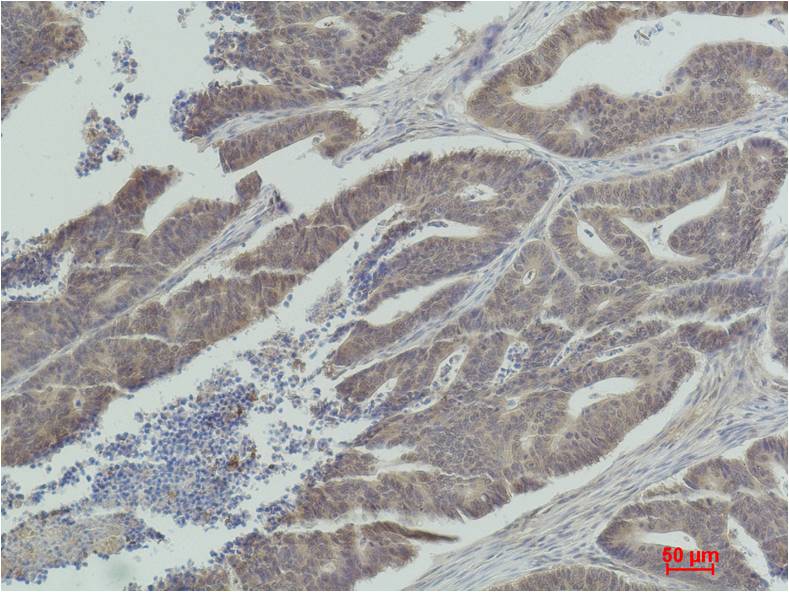

Product name: MEK1 Rabbit pAb

Dilutions: WB 1:1,000-2,000?? IHC? 1:100-200

Background: MEK1 and MEK2, also called MAPK or Erk kinases, are dual-specificity protein kinases that function in a mitogen activated protein kinase cascade controlling cell growth and differentiation. Catalyzes the concomitant phosphorylation of a threonine and a tyrosine residue in a Thr-Glu-Tyr sequence located in MAP kinases. Activates ERK1 and ERK2 MAP kinases.